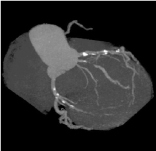

心臓冠動脈VR -

心臓冠動脈MIP -

CTで撮影した心臓の血管の立体像です。 -

左と同じ患者様です。(真ん中に狭い血管が見つかりました) -

同じ患者様のカテーテル検査の写真です。(CTと同じ所に狭い部分があります) -

狭くなっている部分にステントと呼ばれる金属の筒を入れて血管の流れが良くなりました。